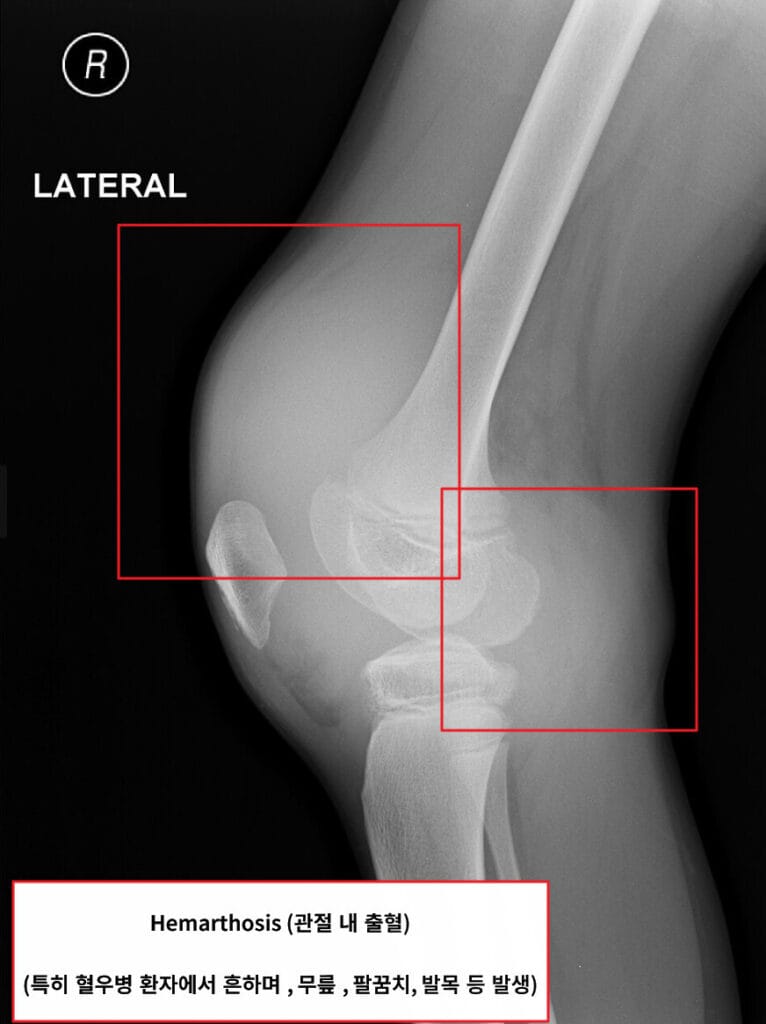

Hemarthosis in X-ray By © Nevit Dilmen, CC BY-SA 3.0, https://commons.wikimedia.org/w/index.php?curid=17605997

혈소판이 일차적으로 상처를 막고 난 뒤, 그 위에 피브린이 형성되어 단단한 혈전이 만들어집니다.이 과정을 담당하는 응고인자에 이상이 있을 때2차 응고장애(Secondary Hemostasis Disorder)라고 합니다. 보통은 출혈이 깊은 조직 (관절 , 근육 내 등) 에서 나타나며, 지연성 출혈(외상 후 시간을 두고 발생)이 특징입니다.

🟪 출혈 위치

관절, 근육, 체강깊은 조직 (관절출혈, 근육 내 혈종 등)

응고인자는 피브린을 형성하여 깊은 곳의 출혈을 막는 역할을 합니다.

🟪 출혈 양상

깊은 출혈, 관절통, 수술 후 멈추지 않는 출혈 등

혈우병 A (Hemophilia A)

내인성 경로의 8번 응고인자의 결핍

• 8번 응고인자(Factor VIII)의 유전적 결핍으로 발생하는 선천성 출혈 질환입니다. 대부분 X-염색체 열성 유전으로, 남성에서 주로 발생합니다.

• Factor VIII이 부족하면 피브린이 충분히 형성되지 않아 관절이나 근육에서 출혈이 잘 생깁니다.